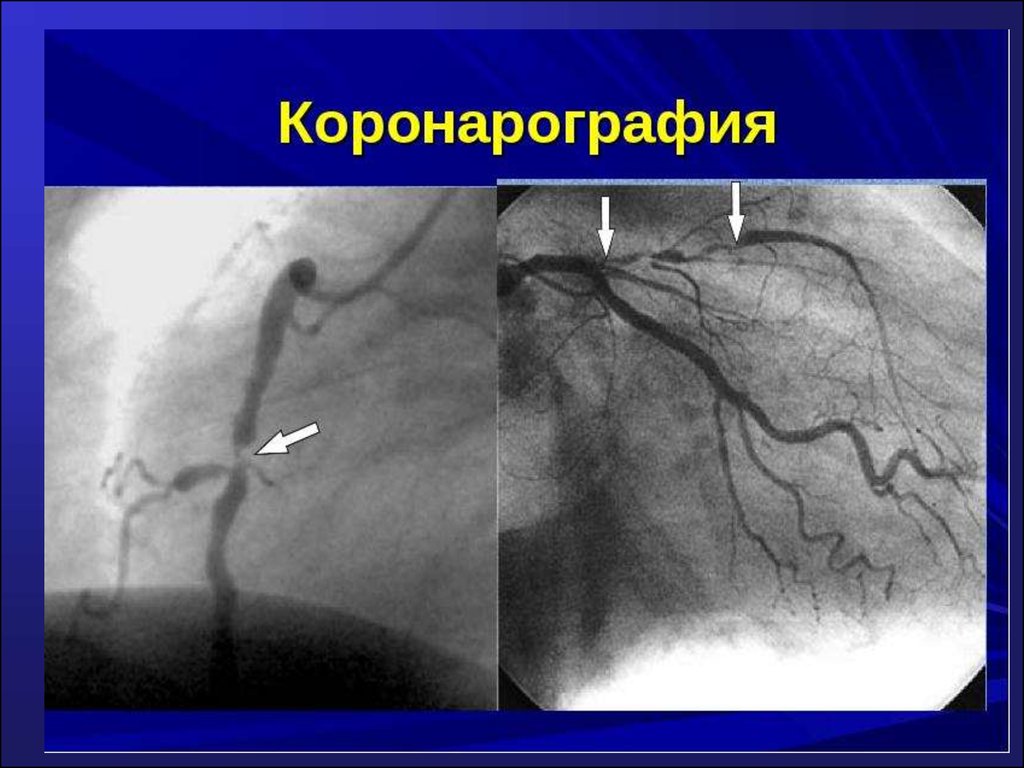

Коронарография

КОРОНАРОГРАФИЯ СОСУДОВ ЛЕВОЙ СЕРДЕЧНОЙ АРТЕРИИ